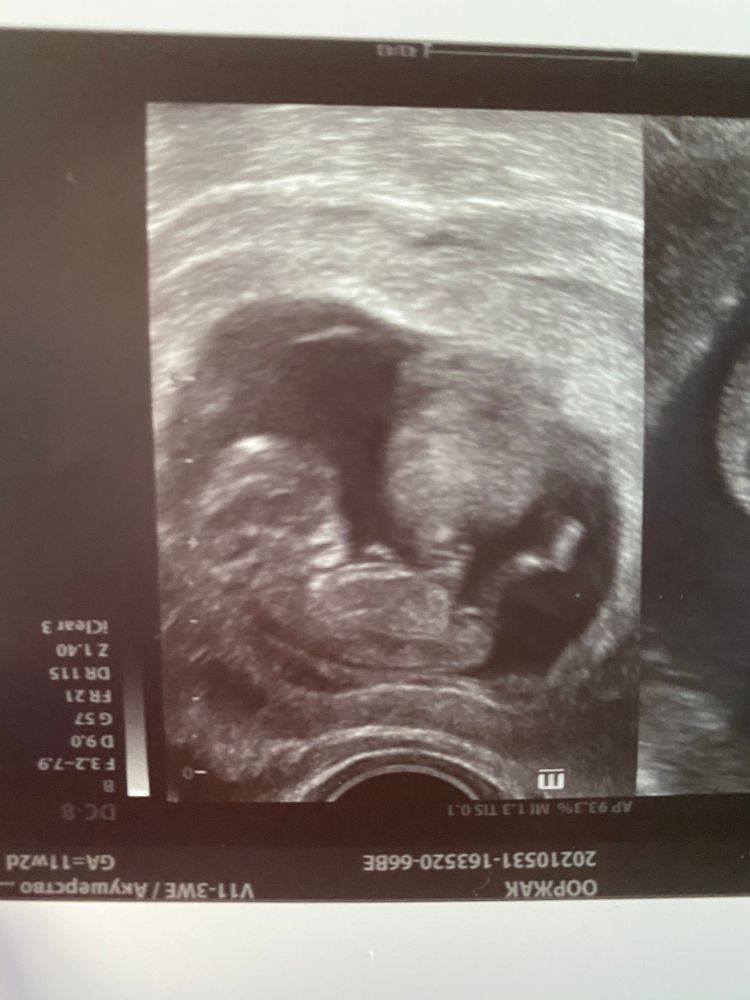

Пол человека😅

Девочка тут

У вас там реально в нужном месте пуповина лежит, её невооружённым взглядом видно. Но по тому, какой аккуратный малыш, предположу больше девочку, чем парня. Но именно бугорок не виден

Половой бугорок вроде бычина девочку ,но если это в 11-12 недель может быть не 100%

Срез так сказать "не половой"( по данному снимку только если погадать( На первом скрининге у самой очень опытный врач на шикарном аппарате на 80 % мне сказал что будет мальчик,и половой бугорок показал и как угол размечается. Но... в 16 Нед - дочка без всяких сомнений. Так что в моем случае не угадали действительно)